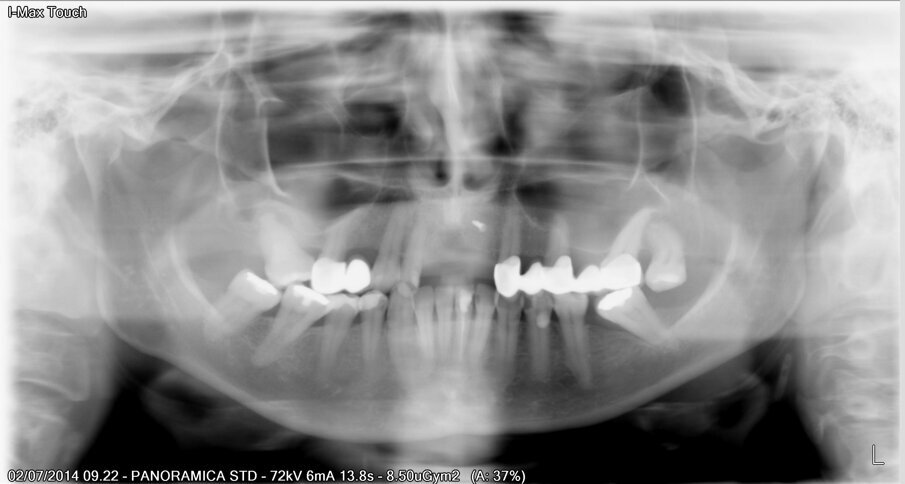

La paziente, donna, di anni 55, era giunta alla nostra osservazione richiedendo una riabilitazione protesica in area estetica a seguito di trauma provocato da un incidente stradale, avvenuto da circa 10 anni, che aveva determinando la perdita di due incisivi superiori in posizione 2.1, 2.2 (Figg. 1, 2).

Fig. 13 - Valutazione del sito rigenerato all’esame radiologico.